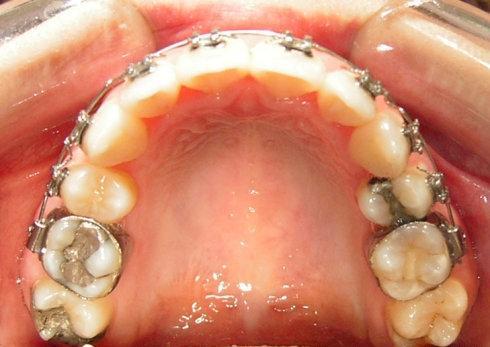

(三)術(shù)前正畸治療

在大多數(shù)情況下,患者需要在手術(shù)前進(jìn)行一段時(shí)間的正畸治療,排齊牙齒,調(diào)整牙齒的傾斜度和位置,為手術(shù)創(chuàng)造有利條件。